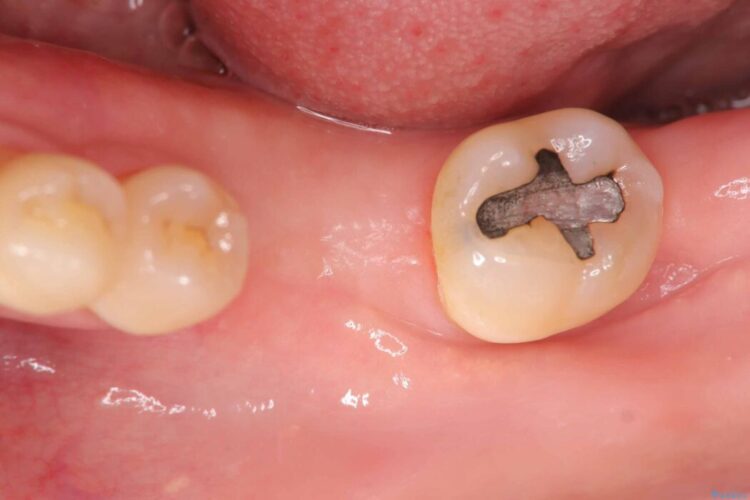

レントゲン検査にて、根尖および側枝付近に骨の透過像が認められました。

さらに精査したところ、根のパーフォレーション(根に穴が開いてしまっている状態)が確認されたため、

患者様と相談のうえ、インプラントにて治療を行うこととしました。